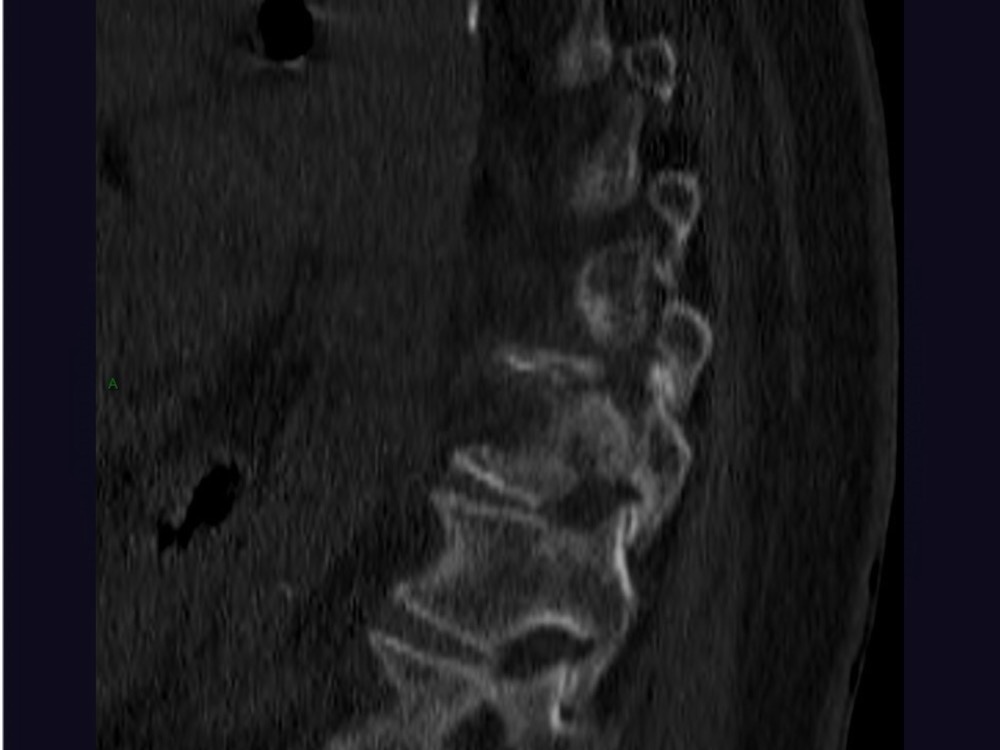

Aboudaram / Thiry 22/06/2020